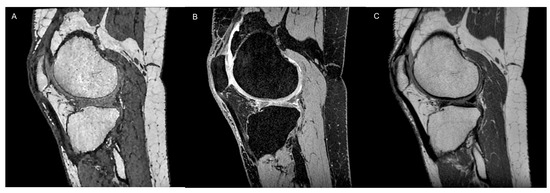

2.1. Conventional MRI

- Omoumi, P.; Mourad, C.; Ledoux, J.-B.; Hilbert, T. Morphological assessment of cartilage and osteoarthritis in clinical practice and research: Intermediate-weighted fat-suppressed sequences and beyond. Skelet. Radiol. 2023, 52, 2185–2198. [Google Scholar] [CrossRef]

- Yang, X.; Li, Z.; Cao, Y.; Xu, Y.; Wang, H.; Wen, L.; Meng, Z.; Liu, H.; Wang, R.; Li, X. Efficacy of magnetic resonance imaging with an SPGR sequence for the early evaluation of knee cartilage degeneration and the relationship between cartilage and other tissues. J. Orthop. Surg. Res. 2019, 14, 152. [Google Scholar] [CrossRef] [PubMed]

- Disler, D.G.; McCauley, T.R.; Kelman, C.G.; Fuchs, M.D.; Ratner, L.M.; Wirth, C.R.; Hospodar, P.P. Fat-suppressed three-dimensional spoiled gradient-echo MR imaging of hyaline cartilage defects in the knee: Comparison with standard MR imaging and arthroscopy. Am. J. Roentgenol. 1996, 167, 127–132. [Google Scholar] [CrossRef] [PubMed]

- Fritz, B.; Bensler, S.; Thawait, G.K.; Raithel, E.; Stern, S.E.; Fritz, J. CAIPIRINHA-accelerated 10-min 3D TSE MRI of the ankle for the diagnosis of painful ankle conditions: Performance evaluation in 70 patients. Eur. Radiol. 2019, 29, 609–619. [Google Scholar] [CrossRef]

- Kijowski, R. 3D MRI of Articular Cartilage. Semin. Musculoskelet. Radiol. 2021, 25, 397–408. [Google Scholar] [CrossRef]